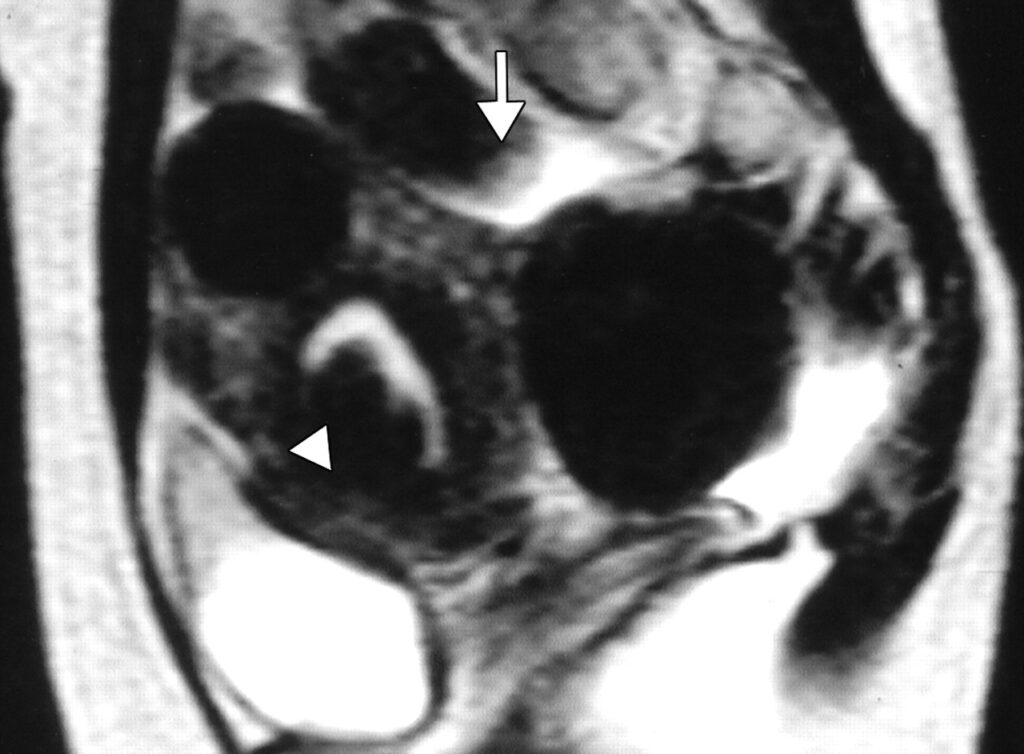

Uterine fibroids are benign tumors that develop in the uterus. While common among all women, fibroids disproportionately affect women of color. Fibroids are the leading cause of hysterectomy, with the average age of women undergoing this major surgery being just 39 years old (Fig. 1).

- UFE has a success rate of 90%, providing relief from fibroid symptoms like heavy menstrual bleeding, pelvic pain, and increased urinary frequency (Fig. 2)